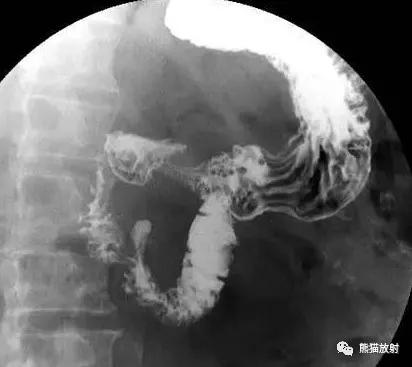

十二指肠球部溃疡,正位片龛影及黏膜纠集

十二指肠球部溃疡,球部变形

十二指肠球线性溃疡。上胃肠道双对比相示变形的十二指肠求内已垂直于肠纵轴的短线条状龛影及纠集的黏膜纹